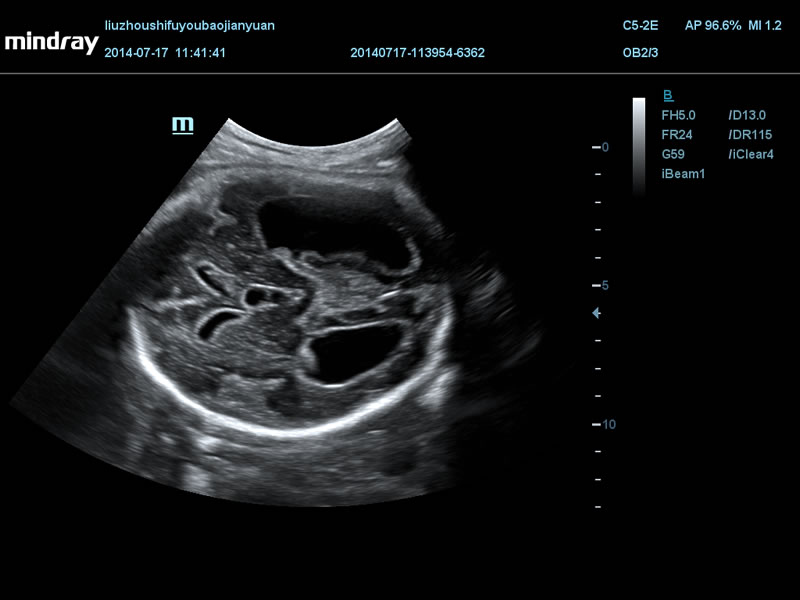

Рот эмбриона, 3D

2 представления одного плодного мешка, Single CRL

14-недельный эмбрион с i Live

Гидроцефалия